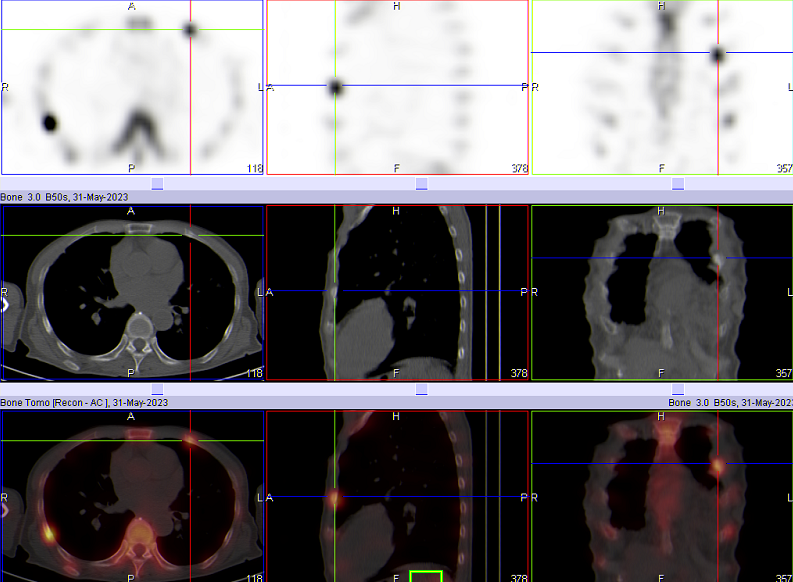

如图所示,胃恶性肿瘤患者,全身骨扫描显示:右侧第6腋肋放射性摄取增高,左侧第3-6前肋放射性摄取增高。进一步加做胸廓断层显像(SPECT/CT)后,影像显示右侧第6腋肋局部放射性摄取增高灶,肋骨骨密度增高,诊断为骨转移;左侧第3-6前肋放射性摄取增高,局部骨皮质皱褶,欠连续,诊断为陈旧性骨折。